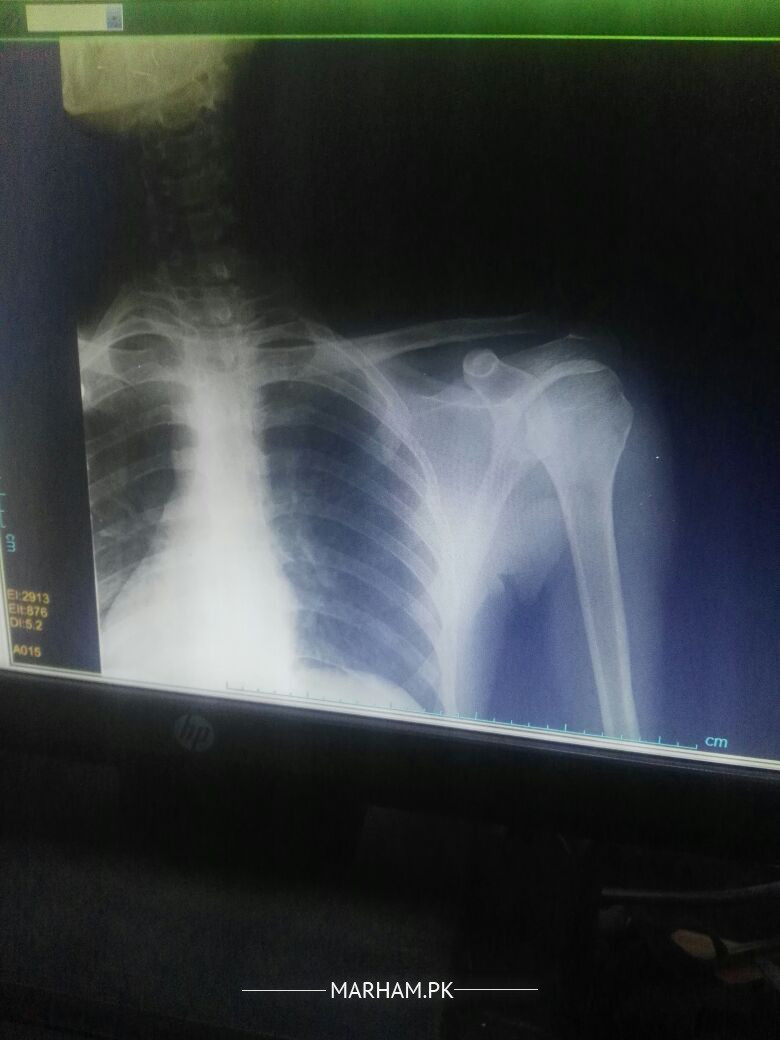

I am Athlete (cricketer) I have very intense shoulder pain while throwing for more than 2 years. I feel little pain in normal routine and even during fast bowling but very intense even after 1 throw. I have had my X RAY and MRI tests (attached) almost normal I think so plz someone guide me I would be thank ful

Attach Photo here: